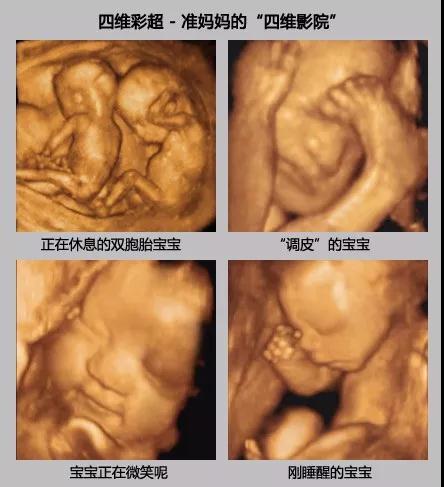

四维彩超能进行宫内写真,让准妈妈看到宫内宝宝的一举一动,亲身体会到宝宝的笑容相貌!而且四维彩超可以把宫内四维彩超宝宝的动态刻录成dvd作为宝宝的0岁写真!作为留念!